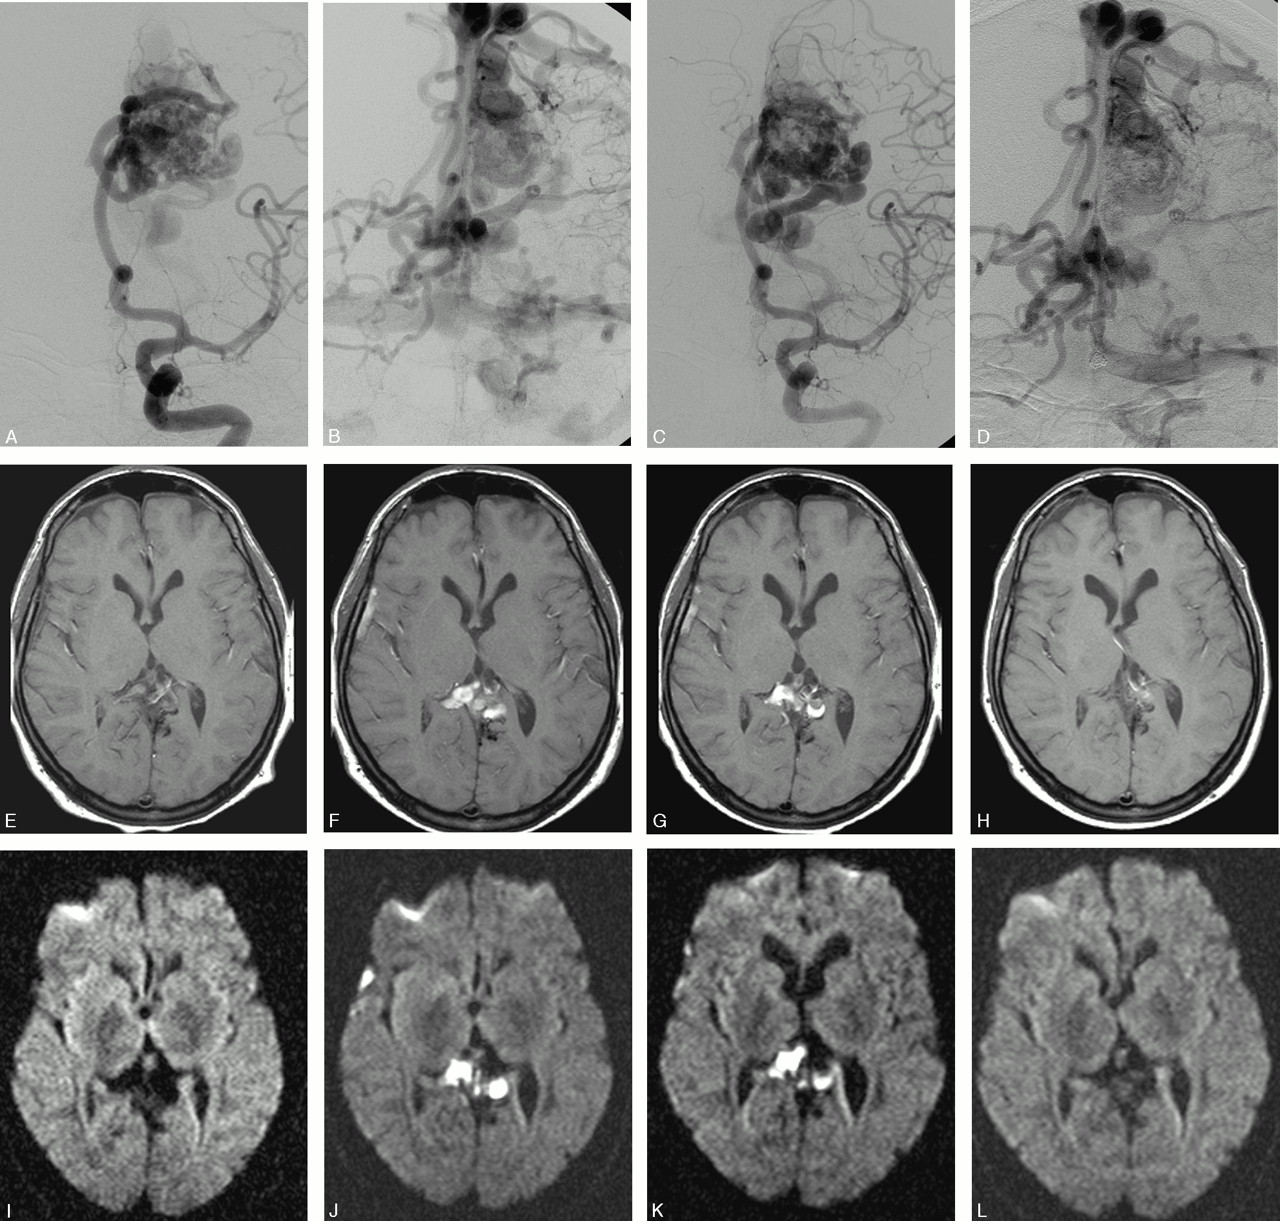

Parieto-occipital AVM before and after treatment.

A and B, Left internal carotid artery (ICA) angiograms in frontal and lateral projections demonstrating a parieto-occipital high-flow AVM with multiple feeders and cortical veins draining to the superior sagittal sinus (pre-embolization).

C and D, Axial rCBFs illustrating the increased perfusion in the AVM nidus (arrow) as well as in the widespread distribution of the cortical draining veins before treatment.

E and F, Almost corresponding rCBFs made after 2 uneventful sessions of embolization. The images show a decrease in AVM nidus size and rCBF in the area of the previously enlarged and draining veins. The patient was then sent for subsequent radiation therapy.

Baseline DWI did not reveal recent ischemia in any of the patients. Three AVMs were too small to be visualized on PI. Seventeen perfusion MR imagings (85%) were abnormal with increased rCBF and rCBV at the site of the AVM as well as along the pathway of the draining veins (Fig 2). The extent of rCBF and rCBV increase within each patient was almost always approximately similar. No major differences were noted between rCBF and rCBV patterns in other areas of the ipsilateral parenchyma versus the contralateral hemisphere, with 2 exceptions. Thus, MTT did not reveal any obvious hemodynamic disturbances in 18/20 MR imagings (90%). Perfusion changes with increased MTT before treatment were seen in 2 patients, engaging large areas of the ipsilateral brain circulation in one patient, and both hemispheres in the other who had a history of ischemic stroke.

A correlation between pre- and post-PI could be made after 40 procedures. A perfusion defect within the embolized portion of the nidus was seen in most patients.

Decreases in rCBF and rCBV within and around the AVM were found after 19/40 procedures. In 3 cases, major reduction of both was demonstrated immediately. rCBF and rCBV remained unchanged after 19/40 procedures. No prolongation of MTT was observed immediately after treatment in any patient. Immediate alterations in rCBF and/or rCBV with secondary ipsilateral decrease of MTT were noted in one patient and bilaterally in one patient; in both patients PI had demonstrated prolonged MTT before embolization. The final MR imaging revealed decreased AVM size and perfusion disturbances in all treated AVMs (Fig 2).

To make an exact definition of the nidus on the PI proved to be extremely difficult, in part because the perfusion disturbances almost invariably exceeded the size of the AVM. The increases in rCBF and rCBV were similar and correlated more to the distribution of the draining veins than to the feeding arteries. Whenever the cortical and draining veins were multiple and diverging toward a long extension of the draining dural sinus, the area of increased perfusion tended to be larger than the size of the AVM (ie, overestimated). Hence, it was almost impossible to evaluate the perfusion pattern in the parenchyma located in close proximity to the nidus or between the draining veins (Fig 2). With few exceptions, no major disturbances of rCBF/rCBV or MTT were found in the parenchyma distally or contralaterally to the AVM before or immediately after treatment. These observations do conflict with the conclusions of Guo et al.31